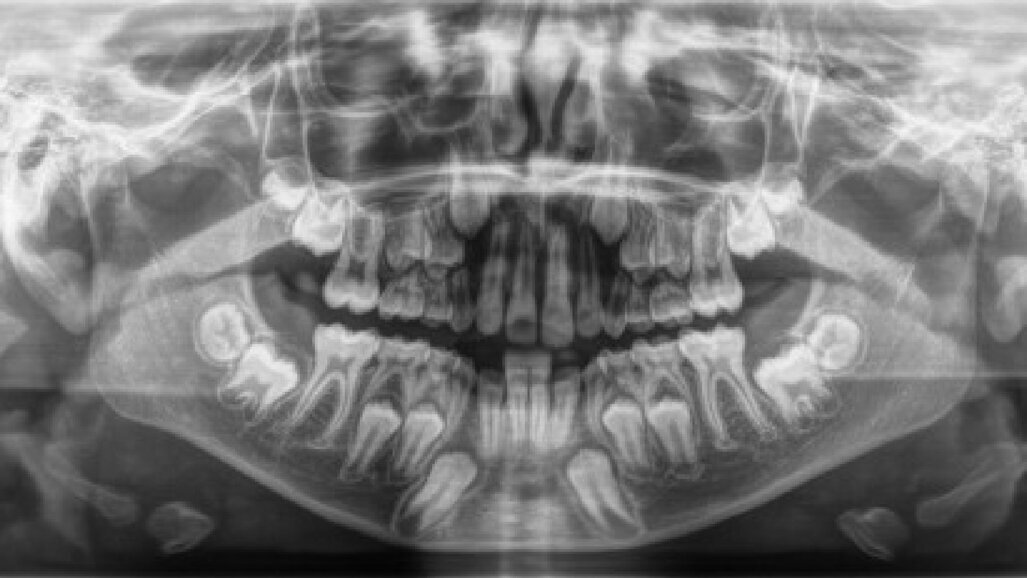

Il paziente, maschio, di 10 anni e mezzo, in dentizione mista. Le arcate dentarie sono in prima classe molare e canina. È presente un overjet di 1 mm e le linee mediane sono centrate. Si osserva un leggero affollamento in entrambe le arcate. Viene raccolta tutta la documentazione clinica per la valutazione del caso ed il successivo trattamento. Si procede alla presa delle impronte per i modelli da studio (Fig. 2). Vengono effettuate l’RX OPT (Fig. 3), la teleradiografia latero-laterale del cranio (Fig. 4) e l’analisi cefalometrica (Fig. 5, Tab. 1). Dopo un anno di terapia intercettiva, è stato eseguito un controllo con una rx OPT per valutare lo stato della permuta dentaria (Fig. 6). All’RX OPT si osserva l’inclusione intraossea con mesio versione dell’elemento 4.3. La CBCT è stata eseguita per valutare la posizione dell’CMI rispetto alle strutture anatomiche vicine (Fig. 7). Il CMI è stato valutato secondo la classificazione di Mupparapu5 nel tipo numero 1. Nella CBCT si osserva parte della corona del 4.3 a contatto con gli apici delle radici degli incisivi inferiori (4.1 e 4.2).

Fig. 6_RX OPT con inclusione dell’elemento 4.3.

Fig. 7_CBCT: a) visione frontale, b) visione sagitale, c) overview, d) visione coronale.